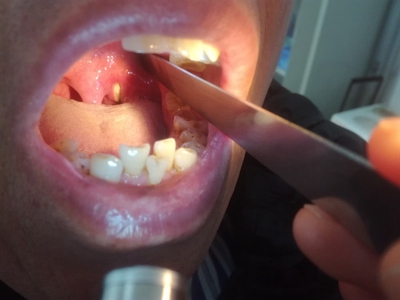

扁桃体结石可在医生指导下使用生理盐水、硼酸溶液进行漱口。结石较小及在隐窝黏膜上的结石可随漱口液消除。对于隐窝内较小的结石,可使用冲洗或吸引扁桃体隐窝的方法清除。

合并扁桃体炎症时,可给以抗生素控制感染,如阿莫西林胶囊、头孢克洛胶囊等。必要时可在医生指导下进行手术治疗,如钳取法、扁桃体剥离取石等。